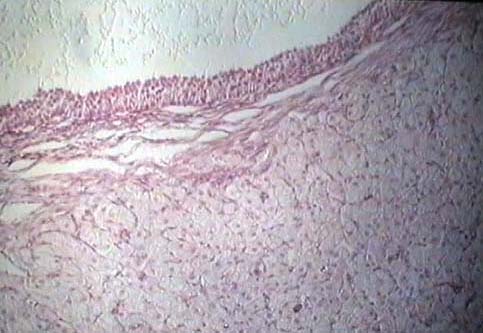

Niere und ableitende

Harnwege

Weiblicher Genitaltrakt